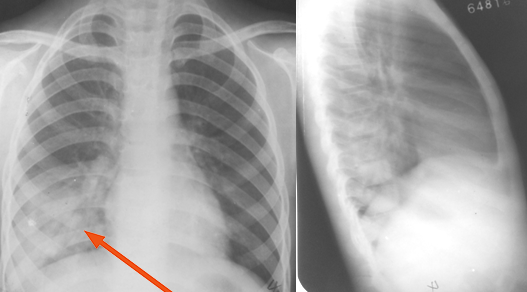

右上、下肺支原体肺炎

图片

胸部正位片示:右上、下肺野肺纹理增粗,可见斑片状阴影,密度较淡,局部呈扇形自肺门部发出(箭头所指)

右肺中叶支原体肺炎

胸部正位片示:右肺中叶肺纹理增粗,见斑片状阴影,密度不均匀,局部呈扇形自肺门部发出(箭头所指)